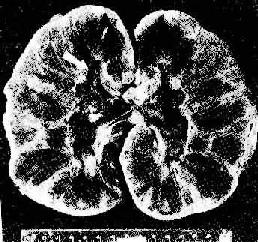

图4-4 肾移植急性排斥反应 肾间质水肿,肾小管上皮细胞变性,间质及毛细血管内有大量单核细胞 (2)血管型排斥反应:主要为抗体介导的排斥反应(CMC,ADCC和免疫复合物形成),往往在稍后出现,以突出的血管病变为特征。表现为肾细、小动脉的坏死性血管炎,可呈弥漫或局灶性分布。免疫荧光证实有免疫球蛋白、补体及纤维蛋白沉积,肾小球毛细血管袢亦可受累。纤维蛋白样坏死的血管壁内常有淋巴细胞、泡沫细胞及中性粒细胞浸润,腔内可有血小板凝集、血栓形成(图4-5)。后期的血管内膜纤维化,管腔狭窄。间质内常有不同程度淋巴细胞、巨噬细胞及浆细胞浸润。肉眼观,肾常明显肿大,呈暗红色并有出血点,有时可出现黄褐色的梗死灶,可伴有肾盂及肾盏出血(图4-6).临床上,移植肾出现功能减退,大剂量免疫抑制剂疗效不佳。

图4-6 肾移植急性排斥反应 肾肿胀,明显出血,肾盏及肾盂中充满血块 3.慢性排斥反应 慢性排斥是反复急性排斥的积累,其突出的病变是血管内膜纤维化,常累及小叶间弓形动脉。动脉内膜纤维化引起管腔严重狭窄(图4-7),导致肾缺血,表现为肾小球毛细管袢萎缩、纤维化、玻璃样变,肾小球萎缩,间质除纤维化外尚有中等量单核、淋巴细胞浸润。肉眼观,肾体积明显缩小,并有多少不等的瘢痕(“小瘢痕肾”)。包膜明显增厚并有粘连。患者肾功能呈进行性减退,其程度与间质纤维化和肾小球、肾小管萎缩的程度成正比。